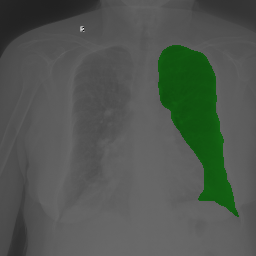

The task of chest organ segmentation is a simple benchmark task in medical image segmentation. In this task, we consider three semantic classes, namely left lung, right lung, and heart. We can easily control the environment to get an insight into the impact of the limited partial labels on various representative partially supervised methods and the efficiency of VLUU. Without specification, the experimental comparison is conducted in such a way that different models use the same network backbone, loss function, training strategy, and the set of hyperparameters.

We use three partially labeled datasets as the training set and one fully labeled as the test set, where the four datasets are collected from four different sources. We choose this setup to simulate the practical scenarios where dataset shift exists, which is a challenging situation for DL models. We use the JSRT dataset as the left lung dataset, denoted as L. We use a subset of the Wingspan dataset containing 18 CXRs as the right lung dataset, denoted as R. We use another subset of the Wingspan dataset containing 18 CXRs as the right lung dataset, denoted as H. We use the rest of the Wingspan dataset as the fully labeled test set, which contains 185 CXRs, and denote it as T. The visual comparison of the data modalities of the four sets can be viewed in Fig. 5. Note, all four sets are collected from 4 different sources (hospitals with different imaging protocols).

5.1.4 Comparison Under Small-Scale Data

It is worth mentioning that, MBG, IMBP, EL, and VLUU are end-to-end methods, i.e. they do not require any auxiliary NNs or multi-stage training procedures. We provide the qualitative comparison of end-to-end methods in Fig. 6(a). VLUU tends to output more realistic masks than the STOA method EL in terms of the location and shape.